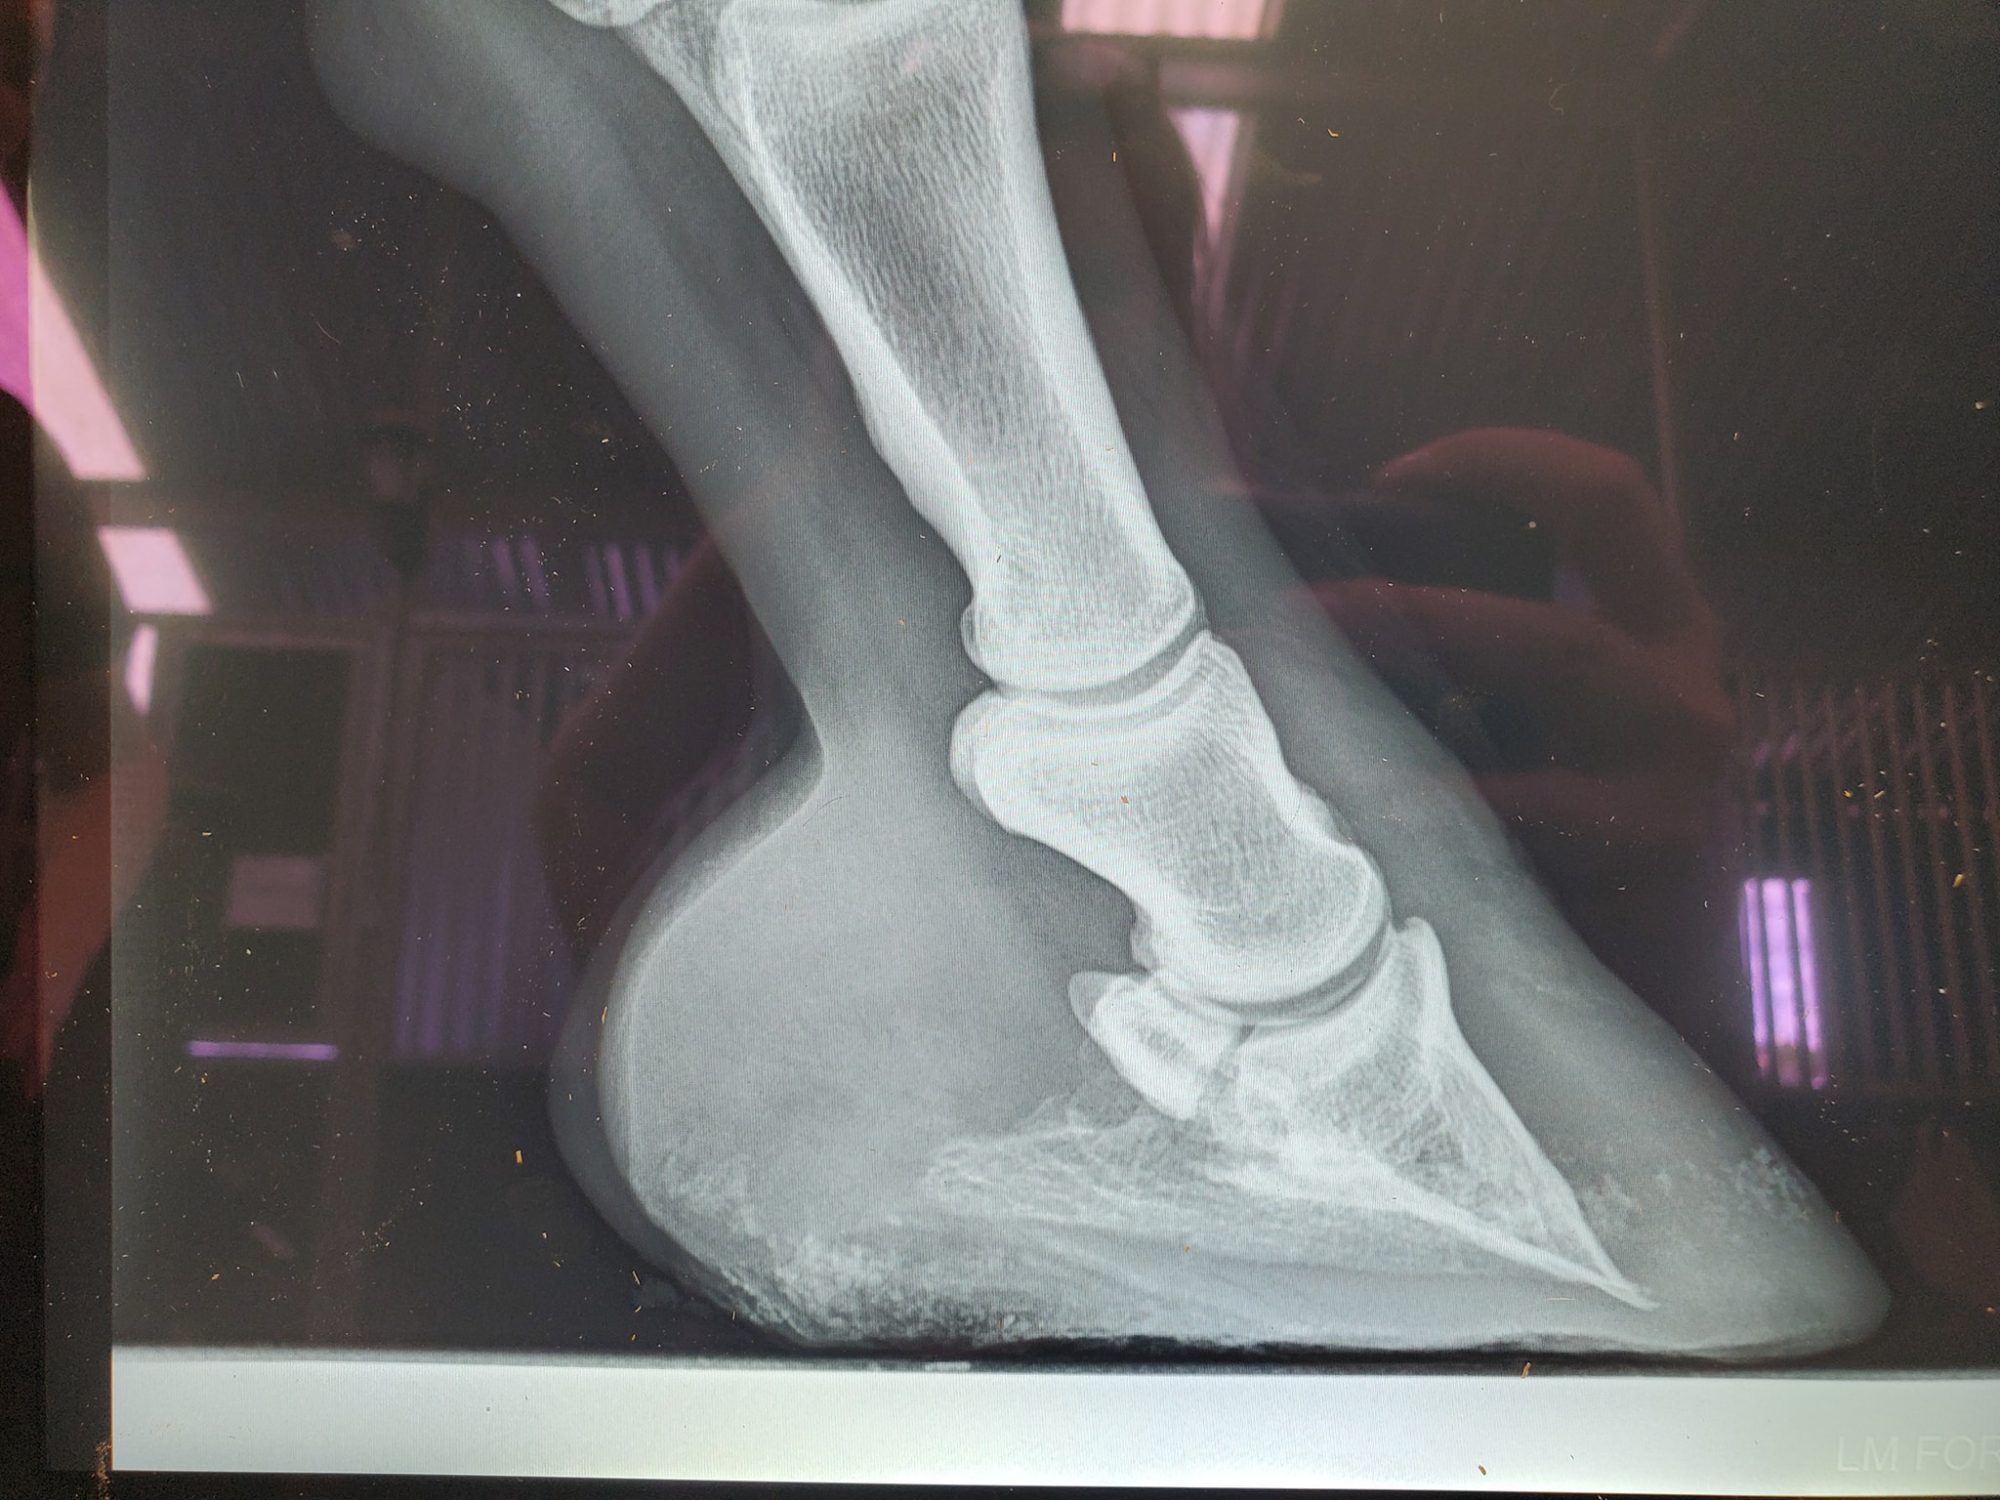

However, the coffin bone is still only half a coffin bone and it is pointed down and sideways (see his most recent x rays). Because he does get uncomfortable sometimes, we give him the very best of hoofcare and very special aluminum shoes.